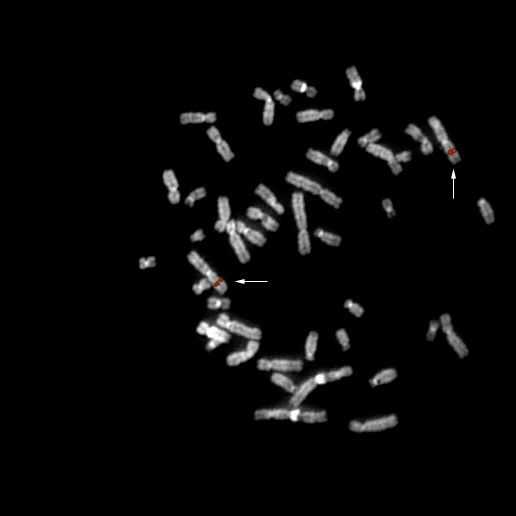

bA24F11